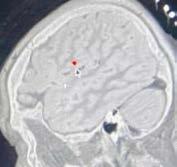

2023 )ويلوي( زوتم l 22 يبظوبأ كنيلك دنلافيلك ىفشتسم عمتجلما ةحص لىع ةيسيئرلا ضارملأا يرثأت نم دحلل ةطشن ةسارد 200 تربلل تضرعت باصم دي عباصأ ديعت ةيبطلا طوبخش خيشلا ةنيدم يبظوبأ كنيلك دنلافيلك ىفشتسم فشك في ةطشن ةيثحب ةسارد 200 نم ثركأ ءارجإ نع دحلا فدهب ،ىفشتسملل عباتلا ثاحبلأا مسق .عمتجلما ةحص لىع ةيسيئرلا ضارملأا يرثأت نم ،تاصصختلا ددعتم يثحب قيرف مسقلا مضي تاساردلا هذه نم ةسارد 60 ءارجإ نم نكتم طبترت ةيويح عيضاوم لىع زكرتو ،2020 ماع في بلقلاو يبصعلاو يمضهلا زاهجلا ضارمأب تلااحلا ضعب في يرجتو ،ضارملأا نم اهيرغو ةيلحلما تاسسؤلما نم ةبخن عم ةكاشرلاب .ةصصختلما ةيميلقلإاو يميداكلأا بتكملل يذيفنتلا سيئرلا تلاق ،يبظوبأ كنيلك دنلافيلك ىفشتسم يف انتمهم لثمتت“ :قزارلا دبع نسوس ةروتكدلا يف يبظوبأ كنيلك دنلافيلك ىفشتسم يف ةلود ناكسل ةيحصلا ةياعرلا تايوتسم ىلعأ ريفوت ةيبطلا طوبخش خيشلا ةنيدم ءابطأ قيرف حجن عيمج تترب نأ دعب حاجنب باصم دي ءانب ةداعإ في لىع هلمع ءانثأ ةنميهلما ىنميلا هدي عباصأ .ةرايس كرحم حيلصت ةيحارج ةيلمع ةقيقدلا ةيومدلا ةيعولأا ةحارج دعت ليصوت ةداعلإ اهيلإ ءوجللا متي ةياغلل ةدقعم ءازجلأا يف ةقيقدلا باصعلأاو ةيومدلا ةيعولأا نأ لبق اهيف ةيومدلا ةرودلا ةداعتسلا ةروتبملا سيئر لاق .مدلا تادادمإ صقن ببسب تومت ابنج لمعلا نع لاضفو .امومع ةقطنملاو تاراملإا نواعتي ،تاصصختلا ددعتملا انقيرف عم بنج ىلإ تاعماجلا عم ىفشتسملا يف ثاحبلأا مسق تامدخ زيزعتل نيرخلآا نييجيتارتسلإا ءاكرشلاو يف رمثتسن نحنو ،عمتجملا يف ةيحصلا ةياعرلا ةيريرسلا ةياعرلا يمدقم نم لبقملا ليجلا ةيميلعتلا اندوهج للاخ نم ،ةيحصلا ةياعرلا ةداقو تاءارجإو ةديدج تاجلاع ريوطتل ،لمشلأا ةيثحبلاو لاجم يف عسوأ تارايخ ريفوتو ةمدقتم ةيصيخشت ناكس ىلع ةدئافلاب دوعي امب ،يئاقولا بطلا راشأ .”ةلبقم ةليوط تاونسل تاراملإا ةلود ايلاح يرجي يثحبلا قيرفلا نأ ىلإ ىفشتسملا يدثلا ماروأو دبكلا ةحص فدهتست تاسارد ثلاث ةلود ينطاومل ةصصخم تاساردلا عيمجو ةنمسلاو يذلاو مونيجلا ىلع امئاق اجهن مدختستو ،تاراملاا .يوونلا ضمحلا وأ مونيجلا تانايب ىلع زكري ققحتلاو جئاتنلا ةنراقم نكمي ،ةيجهنملا هذه ربع ةديدجلا تاجلاعلا راكتبا ةريتو عيرست ضرغب اهنم هذهل ةصصخملا ةيحصلا ةياعرلا تارايخ ريفوتو كنيلك دنلافيلك ىفشتسم ثحيو .ضارملأا يف ةكراشملل ليجستلا ىلع روهمجلا يبظوبأ هذه حاجن لفكي امب ،ةلبقملا ةيريرسلا براجتلا .ةحومطلا دوهجلا ىلإ تفل يبظوبأ كنيلك دنلافيلك ىفشتسم لايربمإ زكرم عم نواعتلاب يرجت ىلولأا ةساردلا نأ ةنمسلا ضارمأ يف ثحبتو ،يركسلل ندنل جديلوك نينطاوملا دنع ينهدلا دبكلا ضرمو يركسلاو ضيلأا تايلمع ىلع ةسارد لوأ ربتعتو ،نييتاراملإا نواعتلاب ،ةيناثلا ةساردلا ىرجت اميف ،مسجلا يف لوح ةينيج ةسارد لوأ يهو ،ةفيلخ ةعماج عم ةحارجو ةنمسلا ضارمأ ىلع زكرتو ،ةيضيلأا ضارملأا ةريخلأا ةديدجلا ةساردلا فدهتستو ،ةنادبلا جلاع ،تايتاراملإا تانطاوملا نيب يدثلا ماروأب ةيعوتلا ةدايزو نييلحملا ناكسلا نيب ضرملا طامنأ ديدحتو ددشو .يدثلل ةيرودلا صوحفلا ءارجإ ةيمهأب يعولا فدهت ثلاثلا تاساردلا نأ ىلع ىفشتسملا ةلود يف ةيبطلا ةياعرلا تايوتسمب ءاقترلإا ىلإ نم ديدعلا ةكراشمب ةنكمم تحبصأ دقو ،تاراملإا ىشامتتو .ةيبطلا ثوحبلاب ةلصلا تاذ فارطلأا ىفشتسم يف ةيثحبلا تاساردلاو عيراشملا ةمراصلا تاداشرلإا عم يبظوبأ كنيلك دنلافيلك لماعتلا متيو ،يبظوبأ – ةحصلا ةرئاد اهتددح يتلا قفو ةيثحبلا عيراشملا هذه يف نيكراشملا عم ةيامحل ةمراص تاءارجإ عابتا عم ةملاسلا ريياعم ىلعأ .تامولعملا ةيرس ىلع ظافحلاو مهتيصوصخ زوين ديلا ةحارجو ةيميمرتلاو ةيليمجتلا ةحارجلا يراشتساو كيردور روتكدلا ةيبطلا طوبخش خيشلا ةنيدم يف مت ،ىفشتسملا ىلإ ضيرملا لصو امدنع“ :ناد ثيح ةحارجلا ءارجلإ تايلمعلا ةفرغ ىلإ ةرشابم هلقن ةبابسلل ةقيقدلا ةيومدلا ةيعولأا عرز ةداعإب انمق تقرغتسا ةيلمع يف رصنخلاو رصنبلاو ىطسولاو عبصإ يف غلابلا ررضلا ببسبو ليللا لاوط ةعاس 12 .”يناثلا مدقلا عبصإب هلادبتسا مت روتبملا ماهبلإا ةيلمع لعج امو ةغلاب تناك ةباصلإا“ :فاضأو لكشب عطقت مل عباصلأا نأ ةدقعم ميمرتلا مت ،لوطم ءارجإ دعبو ديلا نم تعلتقا لب يوتسم .”حاجنب رصنبلاو ىطسولاو ةبابسلا ميمرت ناد روتكدلا شقان ،ةثلاثلا عباصلأا ميمرت حاجن دعب تارايخلا نم ديزملا ضيرملا عم يبطلا قيرفلاو ءارجإ ىلع ضيرملا رقتساو هماهبإ ميمرت ةداعلإ عبصلإا نم ةقيقدلا ةيومدلا ةيعولأا لقن ةيلمع هدي يف ماهبلإا ءانب ةداعلإ ىرسيلا همدقل يناثلا دعب حاجنب ةيلمعلا ءابطلأا ىرجأف ،ةباصملا ىنميلا ةثلاثب ديب ضيرملا ىظحيل ،ةباصلإا نم عيباسأ ةثلاث .ةيمويلا هماهم يف اهلامعتسا هنكمي ماهبإو عباصأ